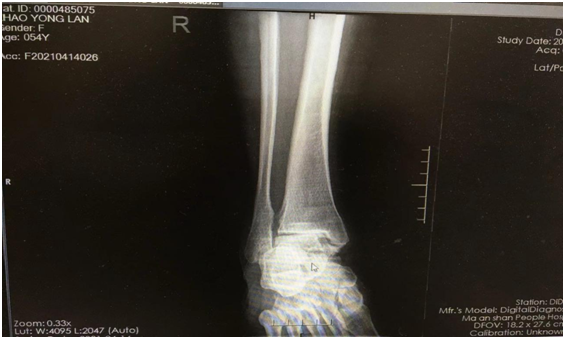

術(shù)前患者踝關(guān)節(jié)關(guān)節(jié)炎的表現(xiàn)